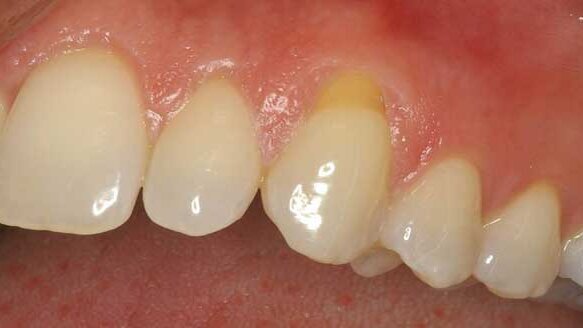

This case describes two areas of recession in a single mouth, thus influenced by identical saliva and oral habits. I used the same cosmetic surgery technique on both areas but used a barrier on only one of the areas (Figs. 3–6).

The 10-plus year outcome (Fig. 7) shows complete root coverage of gingiva on tooth #11, where the barrier collagen TranZgraft was used. The adjacent bicuspid #12 had the same coronal repositioned gingival flap procedure at the same time but without use of the connective tissue barrier.

The results clinically demonstrate that use of a barrier helped achieve complete restoration of gingiva tissue on previously recessed root. The same technique in this case, without the use of a barrier membrane, results in no root coverage (Fig. 7).

This particular case would appear to confirm that barriers aid in predictability of root coverage when using this cosmetic surgery technique.